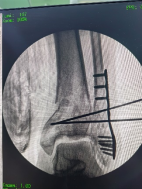

透視檢查骨折端

控制機器人牽引斷端,可見關(guān)節(jié)間隙恢復。